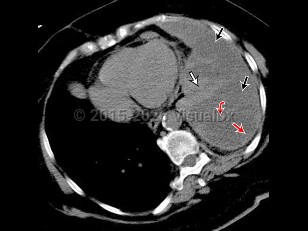

Clinically, effusions may be categorized as either transudates or exudates. Thoracentesis and laboratory evaluation as well as radiographic characteristics distinguish between these types.

History and imaging findings may support one etiology of pleural effusion over another, but analysis of the pleural fluid provides more definitive diagnosis as well as therapeutic management in cases where the pleural effusion is impeding respiratory status.